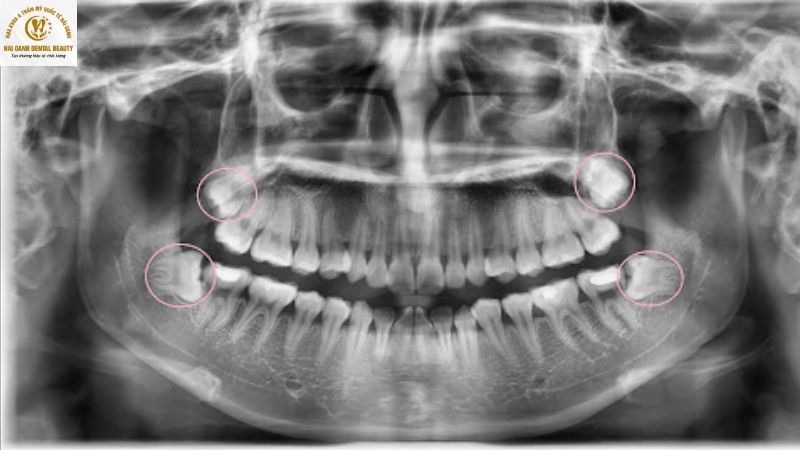

- Vị trí của răng khôn: Răng khôn nằm ở cuối cùng của cung hàm, gần sát xương quai hàm. Nó không tham gia vào chức năng ăn nhai chính và không có vai trò nâng đỡ cấu trúc khuôn mặt. Do đó, việc loại bỏ chiếc răng này không gây ra sự xô lệch đáng kể đối với các răng còn lại hay cấu trúc xương mặt.